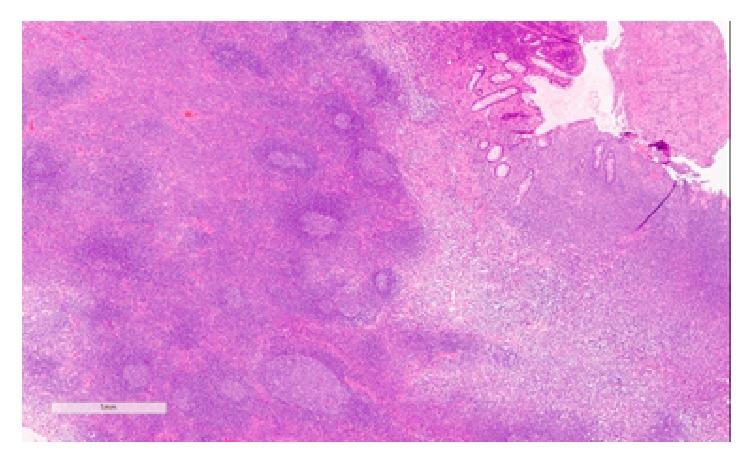

Benign lymphoid polyps are uncommon lesions of the small bowel and the colon to a lesser degree that are mostly found in children. There are only few reported cases in adults in which the lesions were predominantly polypoid and described as lymphonodular hyperplasia. We present a case of a large benign lymphoid polyp in the transverse colon of a 64-year-old lady who was referred to our care for a history of alteration in her bowel habit and anemia. Colonoscopy showed a 3 cm (Paris 1p) friable polyp which was excised and retrieved. Histopathology examination confirmed its benign nature supported by immunohistochemical studies. Benign lymphoid polyp is a rare condition posing a diagnostic challenge as it can be misinterpreted as a malignant lesion.